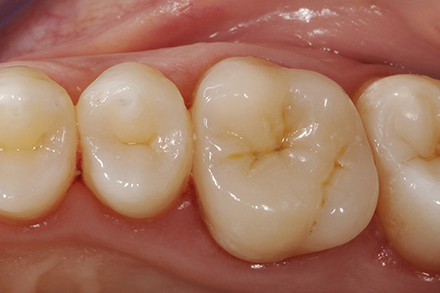

Overlay immediately after cementation with natural teeth still dehydrated.

Check-up - 15 days after successful reconstruction.